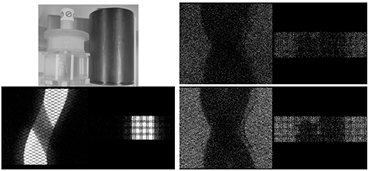

3.1. Rebinning of emission and transmission data

A phantom study was performed to demonstrate the ability to separate the emission and transmission data. A uniform phantom (20 cm diameter × 26 cm in height) with ~1 mCi of activity was placed on the bed next to a cold CT calibration phantom. Figure 4 shows the sinograms acquired simultaneously. The emission sinogram (bottom left) shows a 10 min acquisition and clearly shows the emission events with the shadowing of the cold CT phantom. The transmission sinogram (right figures) shows the collected data also for 10 min and separated by the gamma energies. In both transmission sinograms, both phantoms in the field of view are visible as well as the bed that the phantoms are placed on. All sinograms in the figures are displayed with the same polarity of greyscale.

Figure 4. Photograph of the experimental setup with hot uniform phantom and cold CT calibration phantom with the corresponding emission sinogram (bottom left) and transmission sinograms of 202 keV gammas (top right) and 307 keV gammas (bottom right).

Standard image High-resolution image3.2. Contamination of transmission data from emission signal

From figure 4, one can observe a noisier 202 keV sinogram when compared to the 307 keV sinogram. A study was performed to see if the transmission data was contaminated by the emission data and if the contamination is a function of emission source activity. 3 uniform phantoms (20 cm diameter × 26 cm in height) with varying activity from no activity to 0.5 mCi and 2.2 mCi were placed in the geometric center of the PET field of view. These phantoms were measured for 1 h and rebinned into the 2 transmission trues sinograms (prompts – delays). A profile across all the sinogram elements with summing over 100 angles and summing of all axial planes are shown in figure 5 for 202 and 307 keV transmission sinograms.

Figure 5. Profiles of the 307 keV (left) and the 202 keV sinograms. Profile is across all elements and sum of 100 angles and sum of all axial planes. No activity (-), 0.5 mCi (*) and 2.2 mCi (◊).

Standard image High-resolution imageThere is some contamination in the 307 keV transmission data around the edge of the object which can be seen as a small mismatch between the profiles. The 202 keV transmission data has more visible contamination from emission data. The tails of the sinogram increases in events further away from the center of the field of view. This may be a result of when the backscattering angle approaches 90° and the energies are close to equal to each other and both events fall into the 202 keV window. The change of the profiles in the region outside the objects boundaries in the cold phantom when compared to the region outside the object in the 307 keV profiles could be a result of the 307 keV photons scattering in the object into the 202 keV energy window.